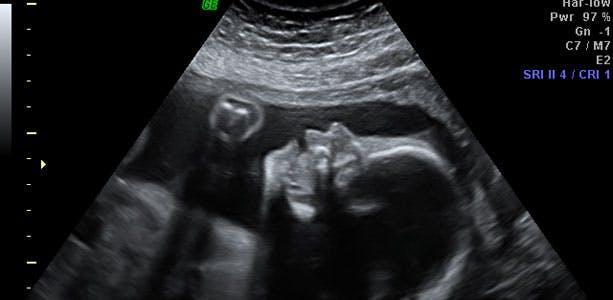

Gravid uge 25: Hver dag i livmoderen er en gave

Hvis din baby bliver født omkring dette tidspunkt, vil det have chancer for at overleve. Men det er sårbart på nuværende tidspunkt, og starten på livet vil blive vanskelig - også på lang sigt kan det blive problematisk, så hver dag, barnet kan blive i livmoderen, er en gave. I slutningen af ugen måler barnet cirka 31 centimeter og vejer omkring 800 gram. Lårbensknoglen er cirka 4,4 cm, og hovedet måler cirka 6 centimeter i diameter.